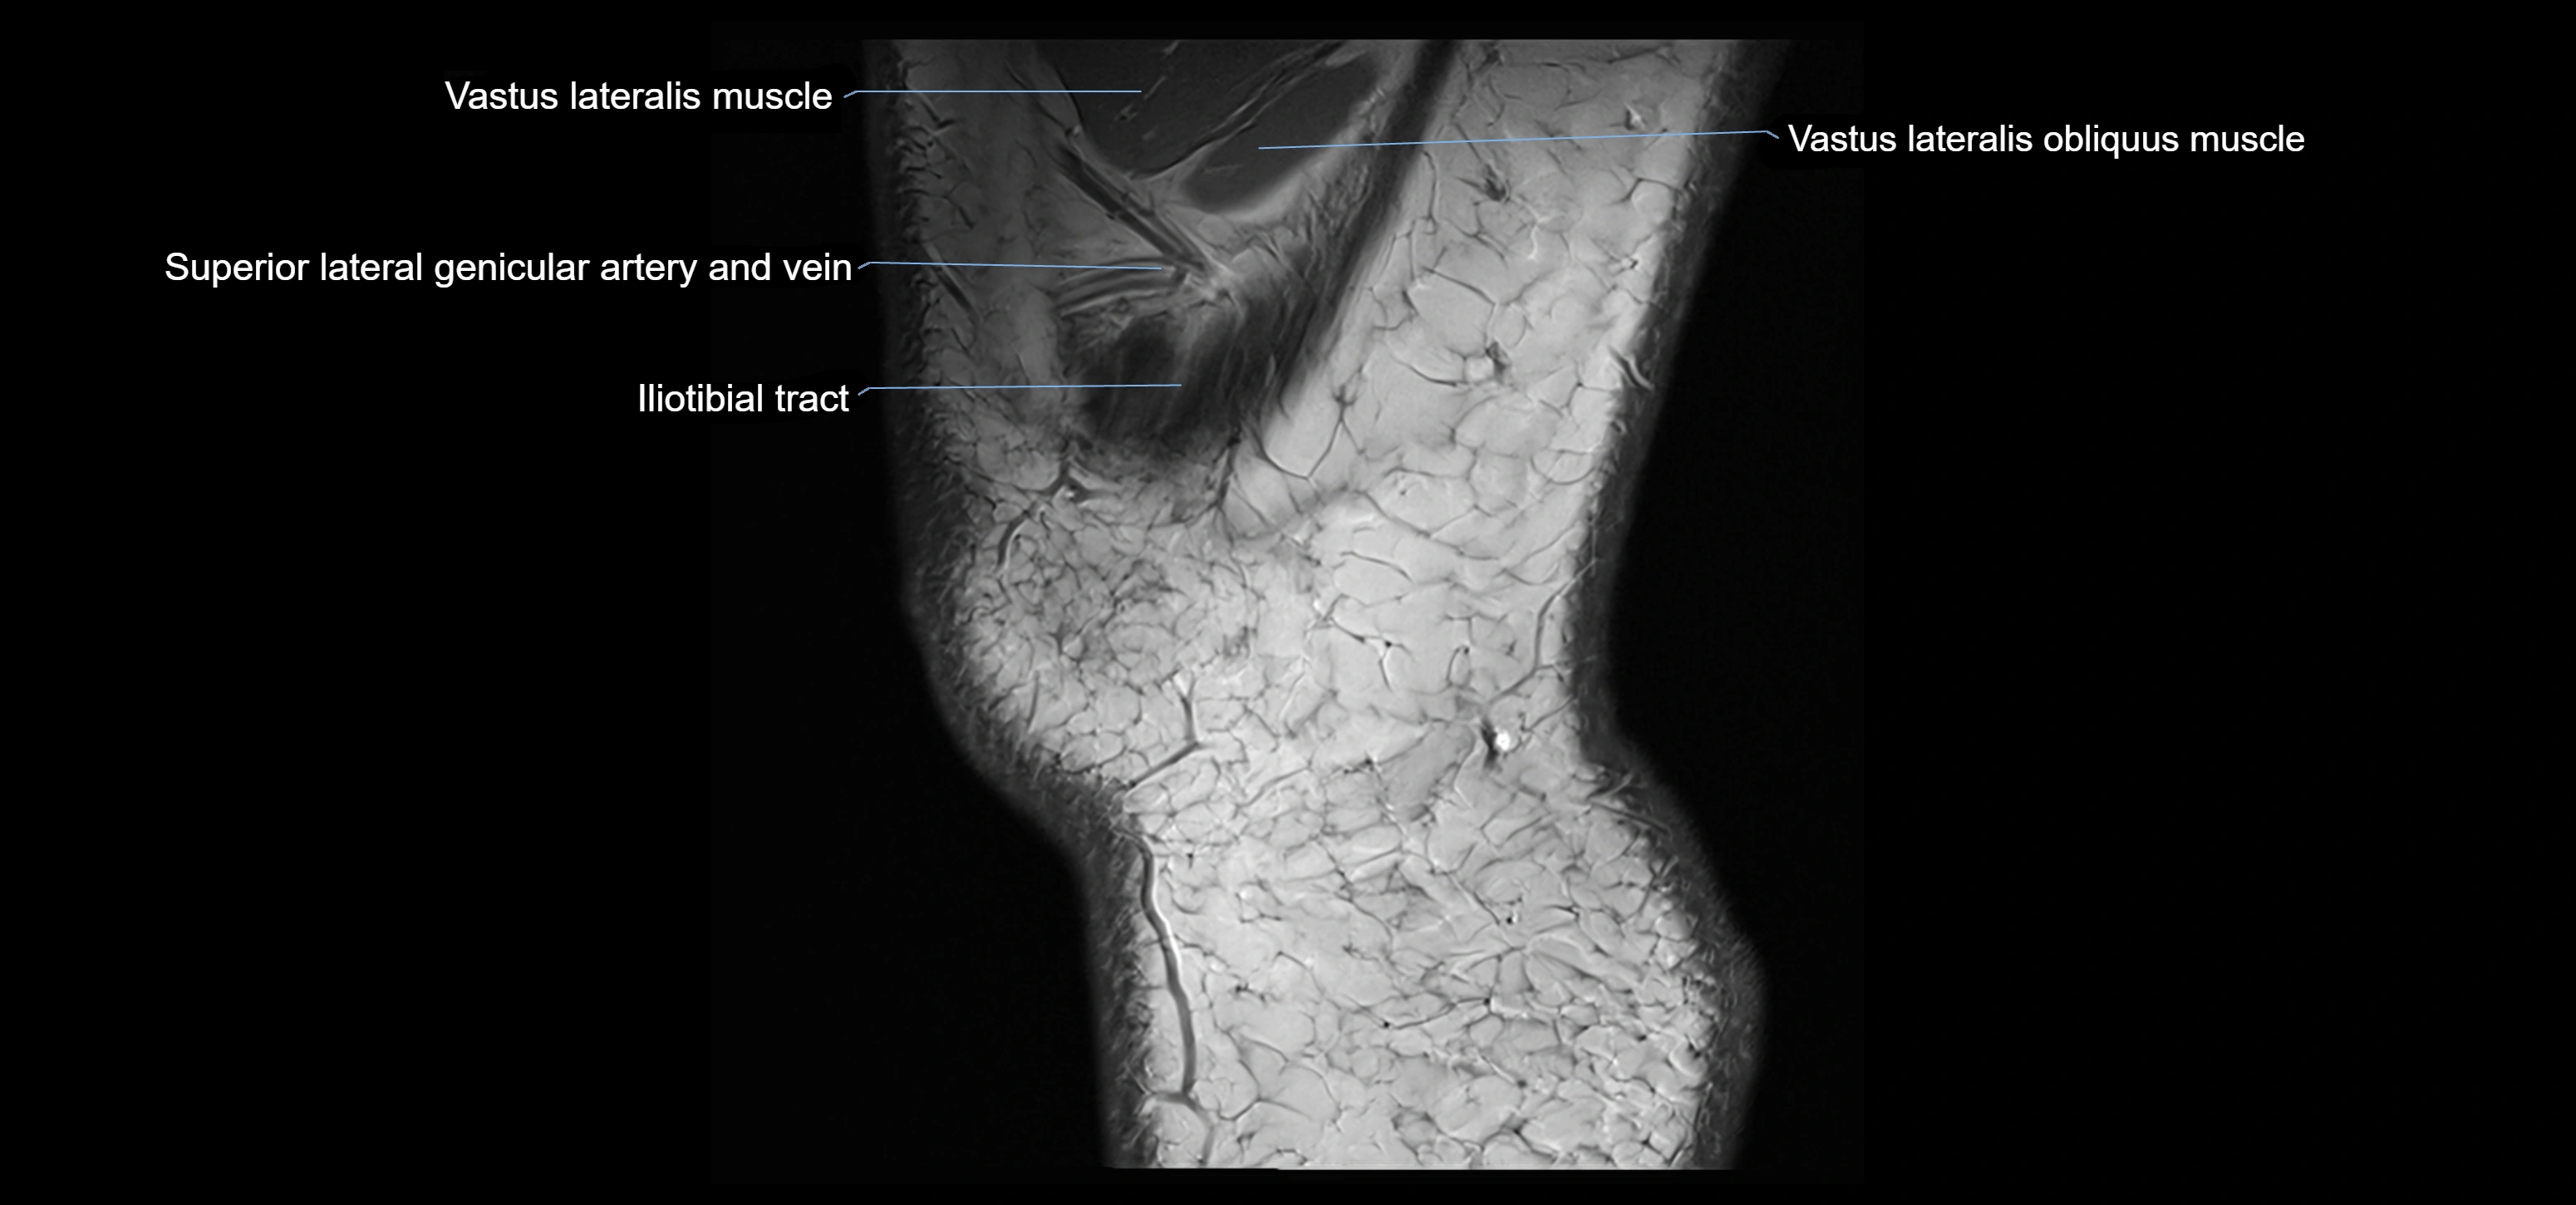

- Vastus lateralis muscle

- Vastus Lateralis Obliquus Muscle

- Superior lateral genicular artery

- Superior lateral genicular vein

- Tubercle of iliotibial tract